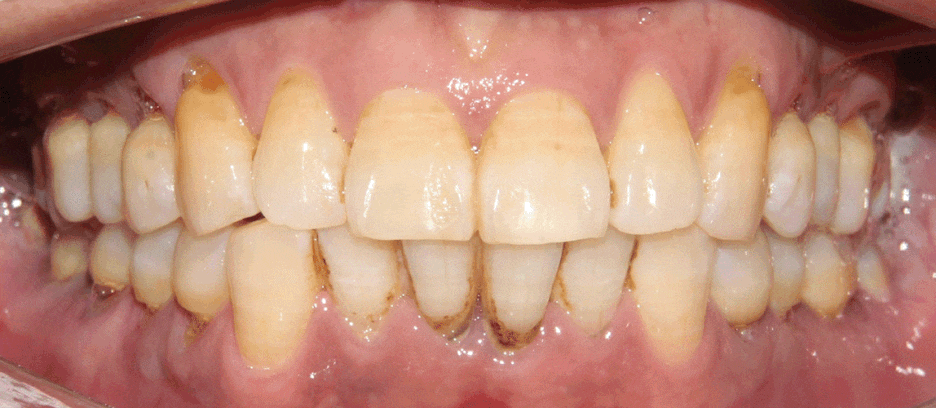

치석제거를 하지 않고 놔두게되면

잇몸이 붓고 염증이 나타나며,

점점 치조골을 녹이게 됩니다.

그렇게 되면 치아가 흔들려서

치아상실로 이어지게 됩니다.

치아상실의 큰 이유는

충치가 아닌 치주질환이 대부분입니다.

그렇기에 치주관리는 중요합니다.

가까운 치과에서

꾸준히 정기검진을 받아서

구강건강을 챙겨주시길 바랍니다.